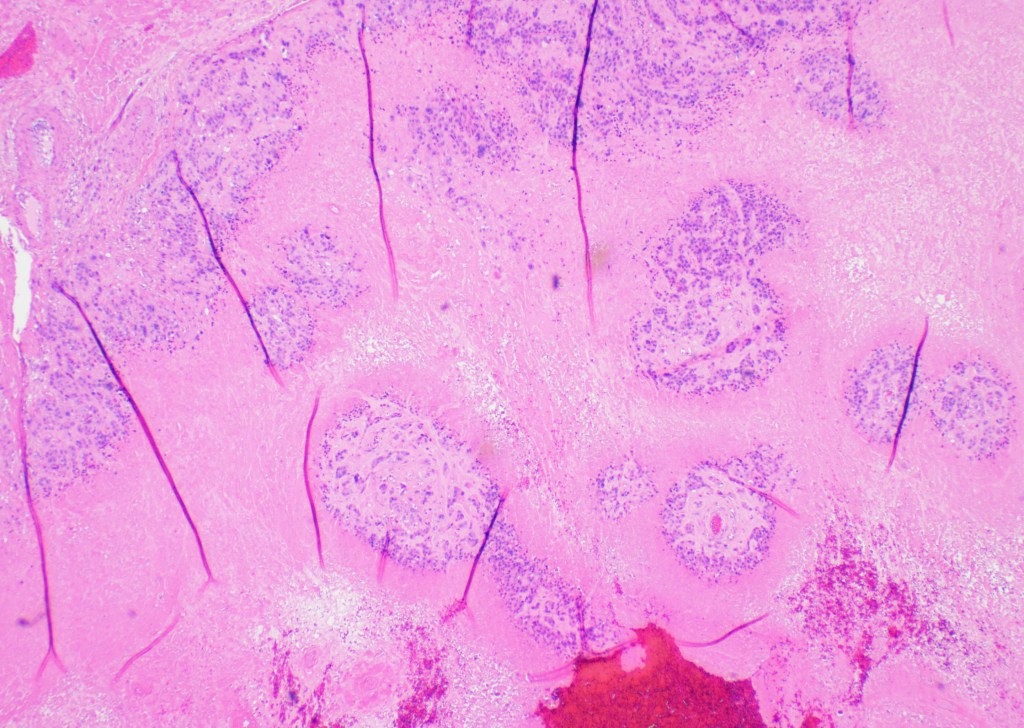

Microscopic examination: the lesion revealed nodular, expansile growth. The nodules were composed of epithelioid cells with abundant eosinophilic cytoplasm, frequent mitotic figures, and the background of necrosis. The nodules and the cells were embedded in the background of hyaline material (Figures 1-4). The cells were positive for GATA-3, alpha inhibin, cytokeratin, and negative for ER, PR, beta-hCG, p16, p53. The diagnosis of the epithelioid trophoblastic tumor (ETT) was rendered. Two years later she presented with new lung nodules. The biopsy showed a metastatic epithelioid trophoblastic tumor with the same immunophenotype. Immunohistochemistry for PD-L1 was positive.

Figure 2

Grossly, the tumor is a distinct lesion or a mass (required for the diagnosis). Microscopically, the cells grow in a nodular pattern with pushing invasion into adjacent structures. The neoplastic cells are large with abundant cytoplasm, arranged in nests and sheets. The mitotic rate is variable, and it ranges from <10 per 10 high-power fields to brisk mitotic activity. High mitotic count is a poor prognostic sign. The background of eosinophilic hyaline-like material is frequently present. Many times, like in our example, extensive geographic necrosis is noted.